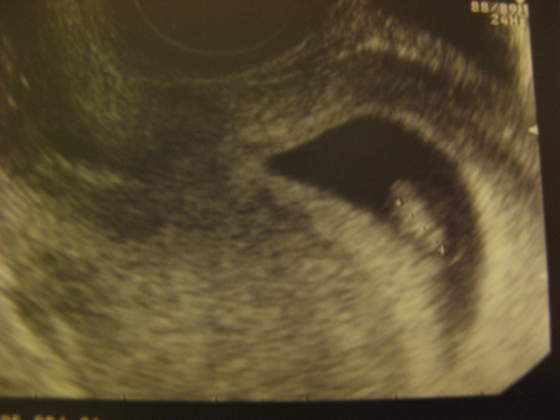

Oj widze ze dla moriam i joanna0984 dzieciaczki sie pleckami odwrucily ;-) Slodziaki!